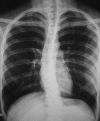

L'inhalation d'un corps étranger (CE) est une urgence médicale courante dans tous les âges. Chez l'adulte, cet accident est beaucoup plus rare que chez l'enfant et survient le plus souvent sur des terrains prédisposés. L'objectif est d’évaluer l'approche diagnostique et thérapeutique de l'inhalation endobronchique d'un CE chez l'adulte. Nous rapportons une étude rétrospective réalisée sur une période de plus de 20 ans (entre Janvier 1994 et Mai 2014) concernant 51 cas de CE endobronchiques de l'adulte. Leur mode de révélation, leurs caractéristiques cliniques, radiologiques et évolutives, la nature de ces CE inhalés sont décrits. Il s'agissait de 8 hommes et 43 femmes dont l’âge moyen était de 28 ans. Un terrain prédisposant est noté dans 13 cas. Le syndrome de pénétration était le maitre symptôme révélateur, retrouvé dans 46 cas. Le siège du CE était bronchique droit dans 30 cas. L'extraction est réalisée par bronchoscopie souple dans 40 cas, rigide dans 3 cas et par chirurgie dans 4 cas. Quatre patientes ont rejeté spontanément le corps étranger. La nature du CE était variable mais restait largement dominée par les épingles à foulards. Nous insistons sur la rareté et la gravité potentielle de l'inhalation de CE qui reste dominée dans notre contexte culturel par l’épingle à foulard chez les jeunes filles. En dehors d'un syndrome de pénétration évident, le diagnostic est souvent difficile faisant recours à la bronchoscopie à la fois diagnostique et thérapeutique. Les mesures préventives restent le meilleur traitement.

Keywords: bronchi; bronchoscopy; chest X-ray; foreign bodies; penetration syndrome.